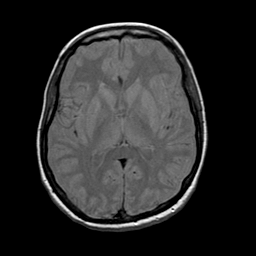

Acute Stroke: proton density-weighted MR -- Slice #14

[Home][Help][Clinical][Tour 1] Slice 14